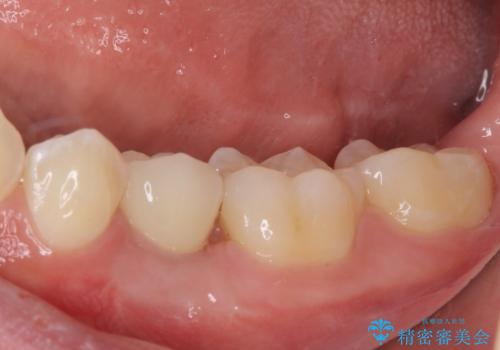

矯正治療が終わるタイミングに合わせてインプラントの埋入を行っていたので、矯正治療を終了すると同時にセラミック補綴治療を行えました。

短期間でしっかりと治療を終えることができました。